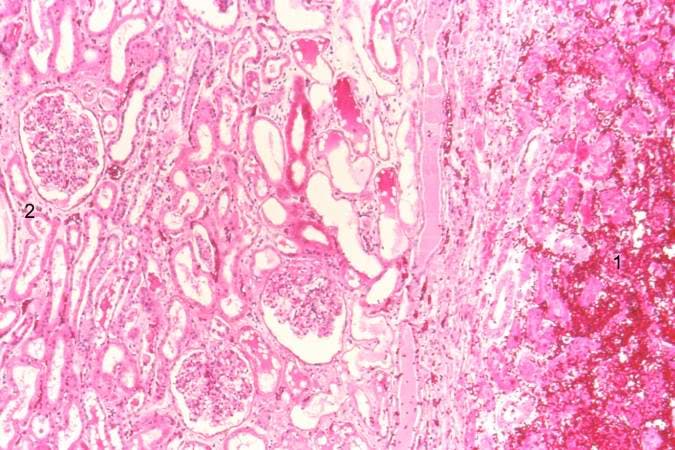

In vascular beds with dual blood supplies, such as the lung or intestine, hemorrhagic (red) infarcts display a combination of coagulative necrosis and blood-filled spaces.

Coagulative necrosis arises when tissue architecture remains intact despite irreversible cell death driven by protein denaturation. It most commonly follows abrupt interruption of blood flow—thrombosis, embolism, advanced atherosclerosis, vasospasm, sepsis-related arterial occlusion, or external compression—leading to ischemia and infarction in solid organs such as the heart, kidney, and spleen. Exogenous toxins, severe thermal injuries, chemical burns, and direct trauma can likewise produce coagulative changes by denaturing intracellular enzymes and structural proteins faster than lysosomal hydrolases can digest them. Clinically, patients present with organ‐specific symptoms and signs of inflammation: crushing chest pain and shortness of breath in myocardial infarction; flank or abdominal pain in renal and splenic infarcts; focal neurologic deficits in cerebral infarcts; or localized swelling, tenderness, and, in cutaneous injuries, blistering. Systemic manifestations often include low-grade fever and leukocytosis. Laboratory studies reveal elevated markers—troponin, creatine kinase, lactate dehydrogenase—when cardiac muscle is involved. Grossly, affected tissues appear pale, firm, and wedge-shaped, whereas microscopically they display homogeneous, eosinophilic cytoplasm, preserved cell outlines, and nuclear changes (pyknosis, karyorrhexis, karyolysis). Recognizing these causal factors and clinical features is essential for early diagnosis and intervention, since prompt restoration of perfusion or removal of the offending insult can limit tissue loss and improve patient outcomes.

The most familiar subtype occurs in solid-organ infarcts—myocardial, renal, or splenic—where abrupt ischemia produces pale, firm, wedge-shaped regions.